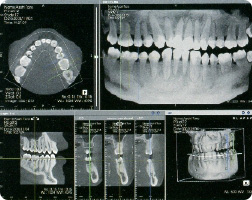

口腔内写真・レントゲン・歯科用CT・口腔内全体を細かく診察するなどし、診断をするための情報を集めます。

当院ではラジオグラフィックガイド作製し、歯科用CTで撮影した患者様の顎骨データを、専用の最新ソフトで解析し、インプラントの最適な位置・方向・本数などを正確にシュミレーションしております。

「ラジオグラフィックガイド」は現在の口の型を元に、歯がない位置へ仮想の歯を理想的に配置したプラスティック製のマウスピースです。インプラント治療を行うためには、最初にコンピューター上での治療計画のもととなる「ラジオグラフィックガイド」を作製します。このグラフフィックガイドを口に入れて、CT撮影をします。